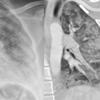

contusion/laceration, pneumo

Date: 07/26/2006

Views: 4475